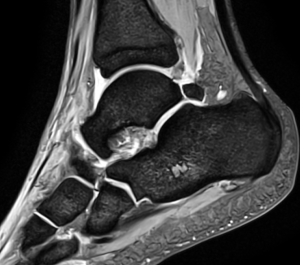

Боль и нестабильность в голеностопном суставе: когда стоит сделать МРТ

Голеностопный сустав ежедневно испытывает значительную нагрузку, обеспечивая опору и подвижность при ходьбе, беге и физической активности. Боль или ощущение нестабильности в этой области часто возникают после травм, подворачивания ноги или перегрузок. В большинстве случаев симптомы постепенно уменьшаются, однако иногда они сохраняются длительное время или даже усиливаются. Это может свидетельствовать о скрытых повреждениях, требующих точной диагностики. Одним из наиболее информативных методов обследования является МРТ голеностопного сустава.

Что именно показывает МРТ голеностопного сустава

МРТ голеностопного сустава позволяет детально оценить состояние связок, сухожилий, хрящевых поверхностей, костного мозга и мягких тканей. Исследование помогает выявить разрывы, воспаление, скрытые переломы, посттравматические и дегенеративные изменения, которые могут быть причиной боли и нестабильности. В ЦМРТС обследование проводится на современном оборудовании, специализированном для МРТ суставов, что обеспечивает комфорт и высокую точность диагностики, необходимую для эффективного лечения.